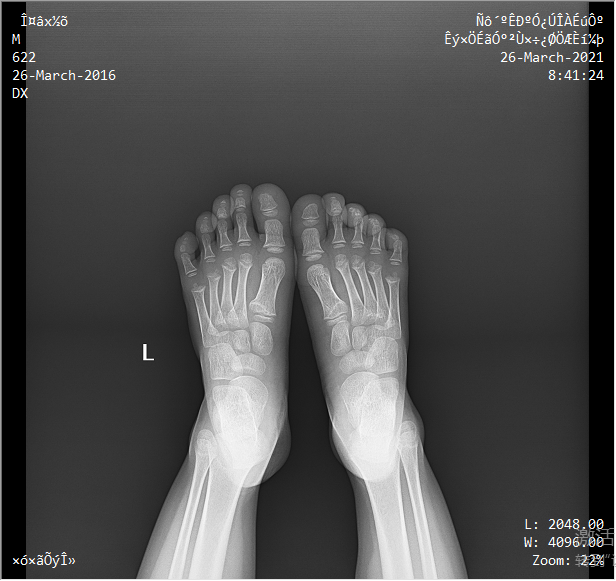

球管上下升降范圍大,便于站立位時足踝負重狀態下的檢查。